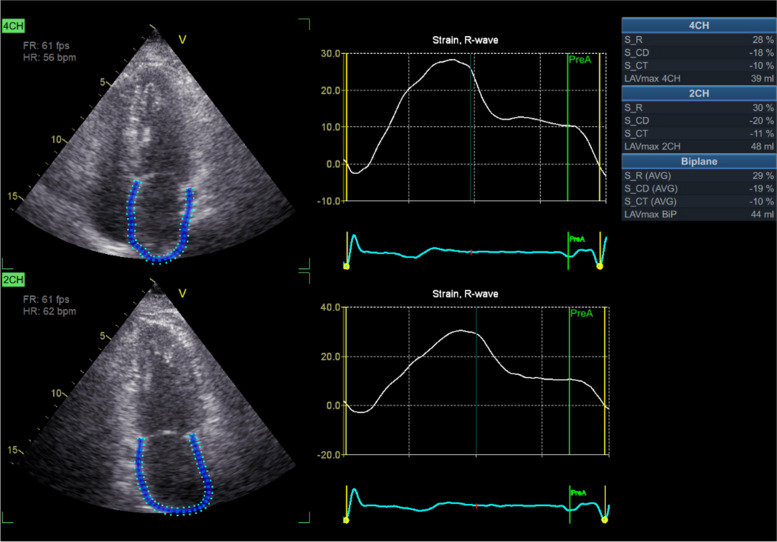

目的:心房性心肌病与心房颤动(AF)密切相关,一些患者在静息状态下没有功能障碍,但在运动时左心房(LA)功能和 LA 容积会发生明显变化。本研究旨在确定窦性心律(SR)患者在运动负荷超声心动图(ESE)检查中的不同体征,包括有阵发性/持续性房颤(PAF)病史和无阵发性/持续性房颤病史的患者:12 个中心共招募了 1055 名窦性心律患者组成前瞻性队列。主要研究队列分为两组:建模组(513 人)和验证组(542 人)。所有患者都接受了 ESE 检查,包括 B 线、LA 容积指数(LAVi)和储期 LA 应变(LASr):结果:两组患者的年龄、静息和应激 LAVi 和 LASr 以及 B 线均被确定为 PAF 的综合检测指标。在整个队列中,除了静息和应激 LAVi 和 LASr 外,区分 PAF 和非 PAF 患者的其他参数包括存在全身性高血压、运动 E/e' > 7、运动时右心室(RV)收缩较差(∆ 三尖瓣环平面收缩期偏移 4),这些参数的敏感性(79%)和特异性(65%)最佳:结论:通过评估 LA 功能储备和容积储备、左心室时相、舒张和收缩储备以及 RV 收缩储备,ESE 可补充静息超声心动图,用于识别 SR 患者既往的 PAF。

Methods: A prospective cohort of 1055 patients in SR was enrolled across 12 centers. The main study cohort was divided into two groups: the modeling group (n = 513) and the verification group (n = 542). All patients underwent ESE, which included B-lines, LA volume index (LAVi), and LA strain of the reservoir phase (LASr).

Results: Age, resting and stress LAVi and LASr, and B-lines were identified as a combination of detectors for PAF in both groups. In the entire cohort, aside from resting and stress LAVi and LASr, additional parameters differentiating PAF and non-PAF patients were the presence of systemic hypertension, exercise E/e' > 7, worse right ventricle (RV) contraction during exercise (∆ tricuspid annular plane systolic excursion < 5 mm), a lower left ventricular contractile reserve (< 1.6), and a reduced chronotropic reserve (heart rate reserve < 1.64). The composite score, summing all 9 items, yielded a score of > 4 as the best sensitivity (79%) and specificity (65%).

Conclusion: ESE can complement rest echocardiography in the identification of previous PAF in patients with SR through the evaluation of LA functional reservoir and volume reserve, LV chronotropic, diastolic, and systolic reserve, and RV contractile reserve.